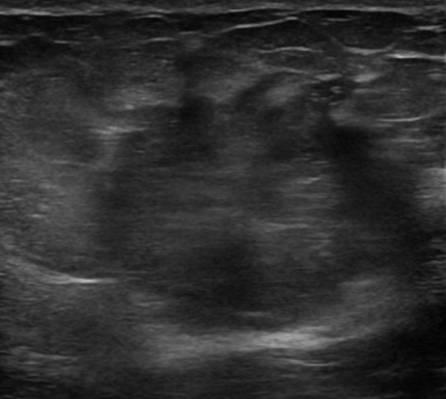

Ung thư vú

» Thông tin: Nữ giới – 76 tuổi.

» Lâm sàng: Khối tuyến vú.